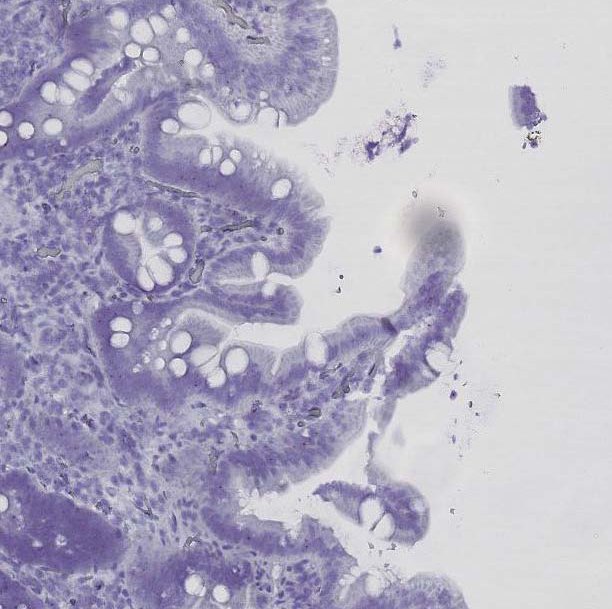

Orain egin dituzten esperimentuetan, gaixotasun zeliakoarekin erlazionatutako gene ez kodetzaile bat aurkitu dute: “lncRNA bat da, lnc13 izena duena”, zehaztu du Bilbaok. Haren funtzioa aztertu dute, eta ikusi dute gaixotasun zeliakoa garatzearekin lotutako geneen espresioa apaltzen dutela. Zeliakoetan, baina, lnc13 oso gutxi dago. "Horren ondorioz, hesteetako hantura eragiten duten geneen espresioa areagotuta dago. Gainera, zeliakoetan ohikoago den aldaera genetikoak erregulazio ahalmena murritzagoa dauka, eta horrek inflamazioa bultzatzen du", esplikatu du Bilbaok.